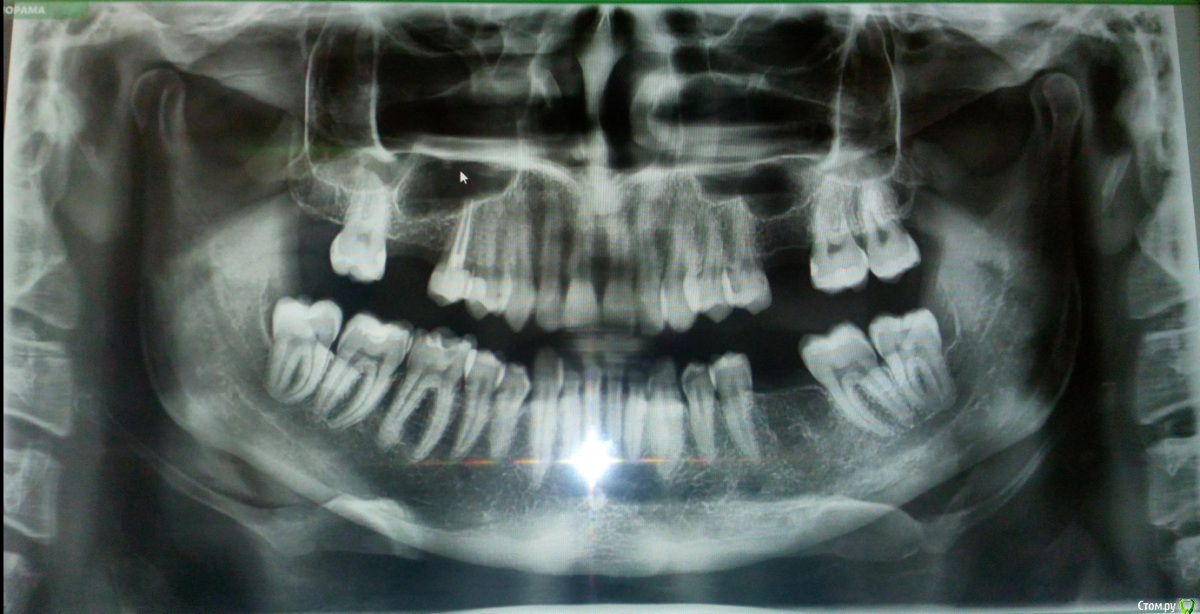

nikita_zn Опубликовано 25 декабря, 2019 Поделиться Опубликовано 25 декабря, 2019 Здравствуйте! Будьте добры рассудите по снимку. Справа и слева верхней челюсти, где вырваны зубы, может ли быть гной в полостях? Стоматолог мне сказал, что лор и хирург должны посмотреть этот снимок и вынести вердикт. И больше меня волнует с правой стороны полость, в виде круга, там был самый плохой зуб. Благодарю. Ссылка на комментарий

Saymon Опубликовано 25 декабря, 2019 Поделиться Опубликовано 25 декабря, 2019 Добрый день. То, что вы видите в виде темных кругов, то это носовые пазухи и нечего страшного в этом нет. Просто такая анатомия у людей. Вы с какими жалобами обратились к стоматологу? Ссылка на комментарий

nikita_zn Опубликовано 25 декабря, 2019 Автор Поделиться Опубликовано 25 декабря, 2019 Ищу воспалительный процесс! Вот и сделал снимок. Подумал, может пазуха воспалилась. И в этой полости гной остался, от вырванного зуба. Ссылка на комментарий

nikita_zn Опубликовано 25 декабря, 2019 Автор Поделиться Опубликовано 25 декабря, 2019 Сейчас на месте удаленного зуба справа, круглое затемнение(как шарик) и в пазухе чувствую жжение, и периодическую заложенность, + температура 37.4. Ссылка на комментарий